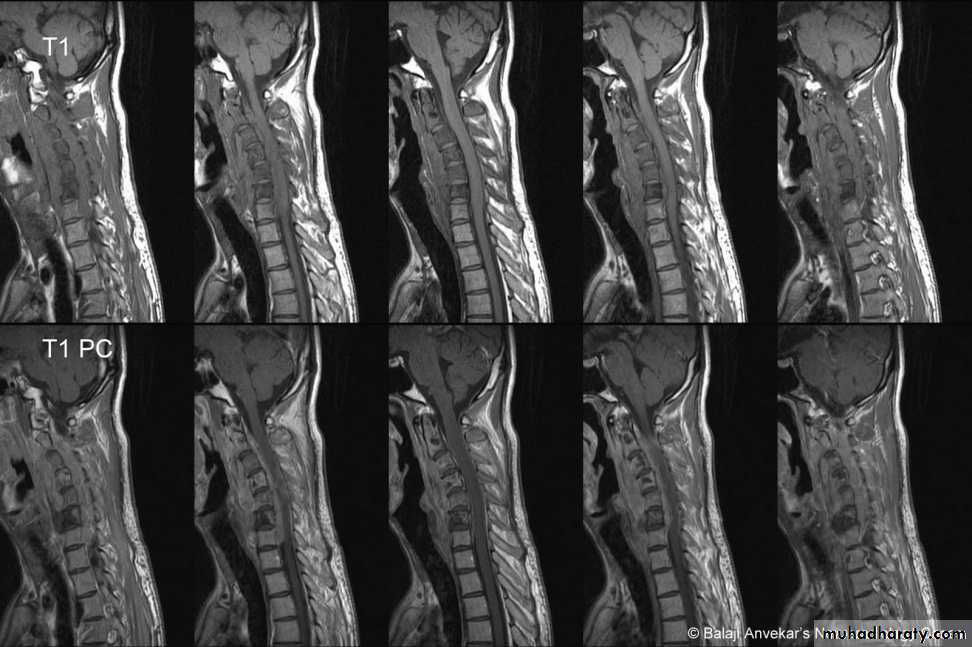

DIAGNOSISX RAY

Anterio posterior X ray radiograph.lateral radiographs with the head in flexion and extension may revealinstability that is not shown in the routine lateral film.

Computed tomography (CT)

and magnetic resonance imaging (MRI).